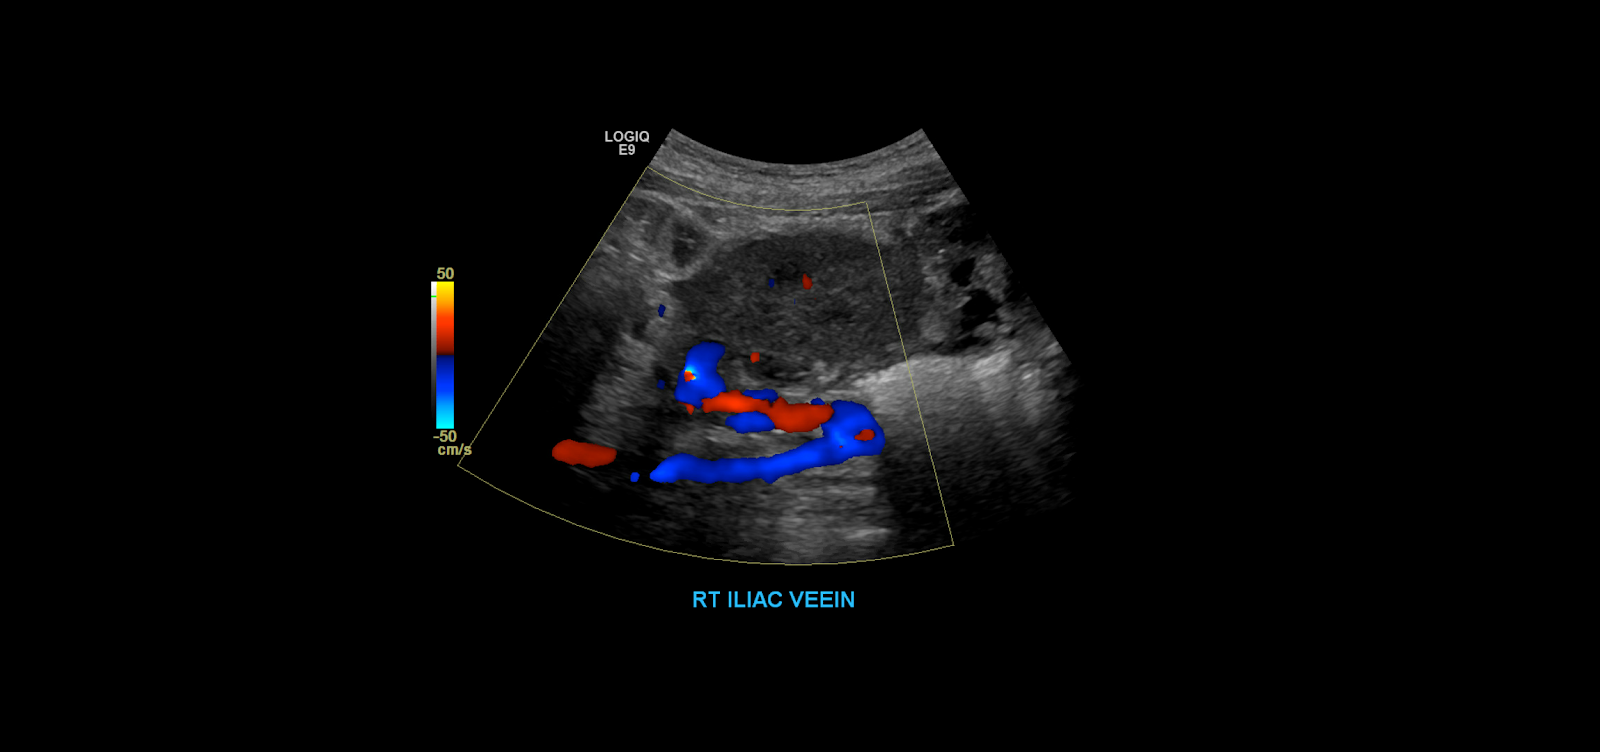

When you’re done examine the kidney in gray-scale you become to take your color spectral Doppler images. Begin with the iliac vessels.

Take gray-scale, color and spectral Doppler of the common iliac artery. Use angle correction 45-60°.

Measure the peak systolic and end diastolic velocities.